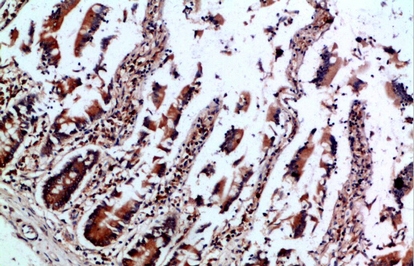

IHC (Immunohistochemisry)

(Immunohistochemistry of paraffin-embedded Human colon tissue using IL-12B p40 Polyclonal Antibody at dilution of 1:200.)